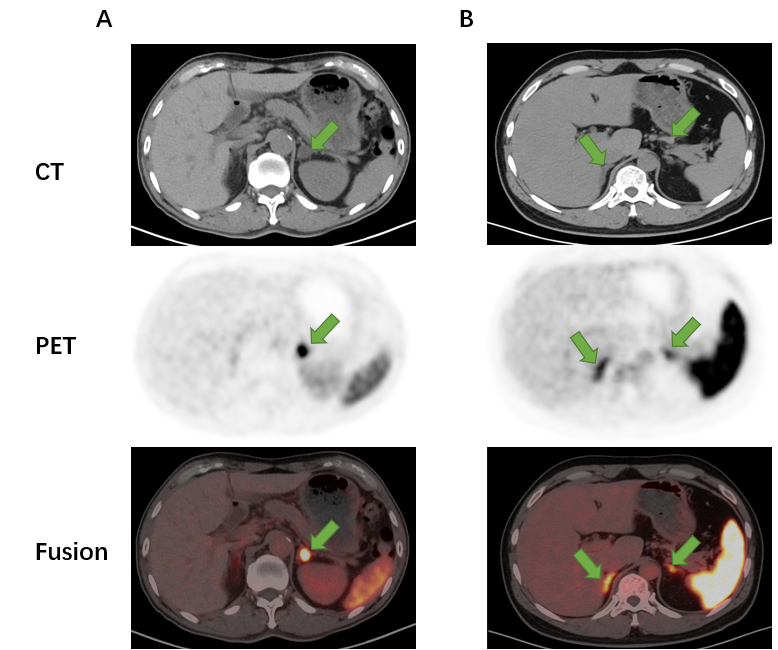

ct(68镓-cxc趋化因子受体4 pet/ct显像)对原发性醛固酮增多症(简称"原